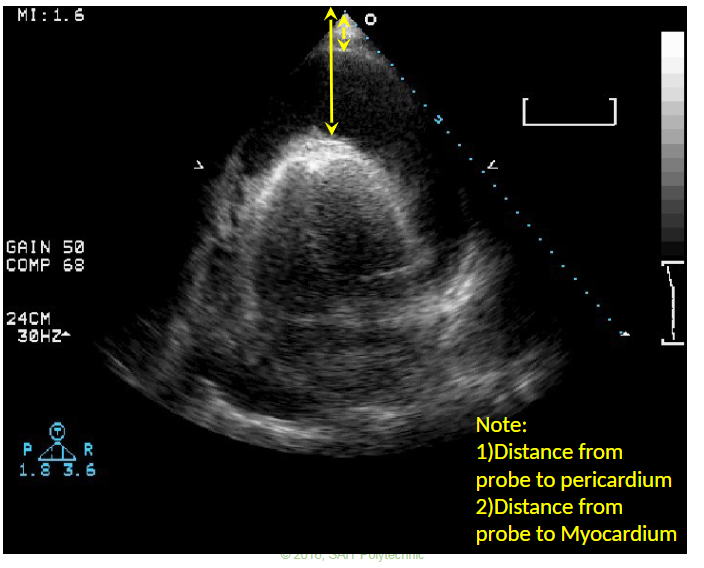

Q

What does this image represent?

A

Pericardiocentesis